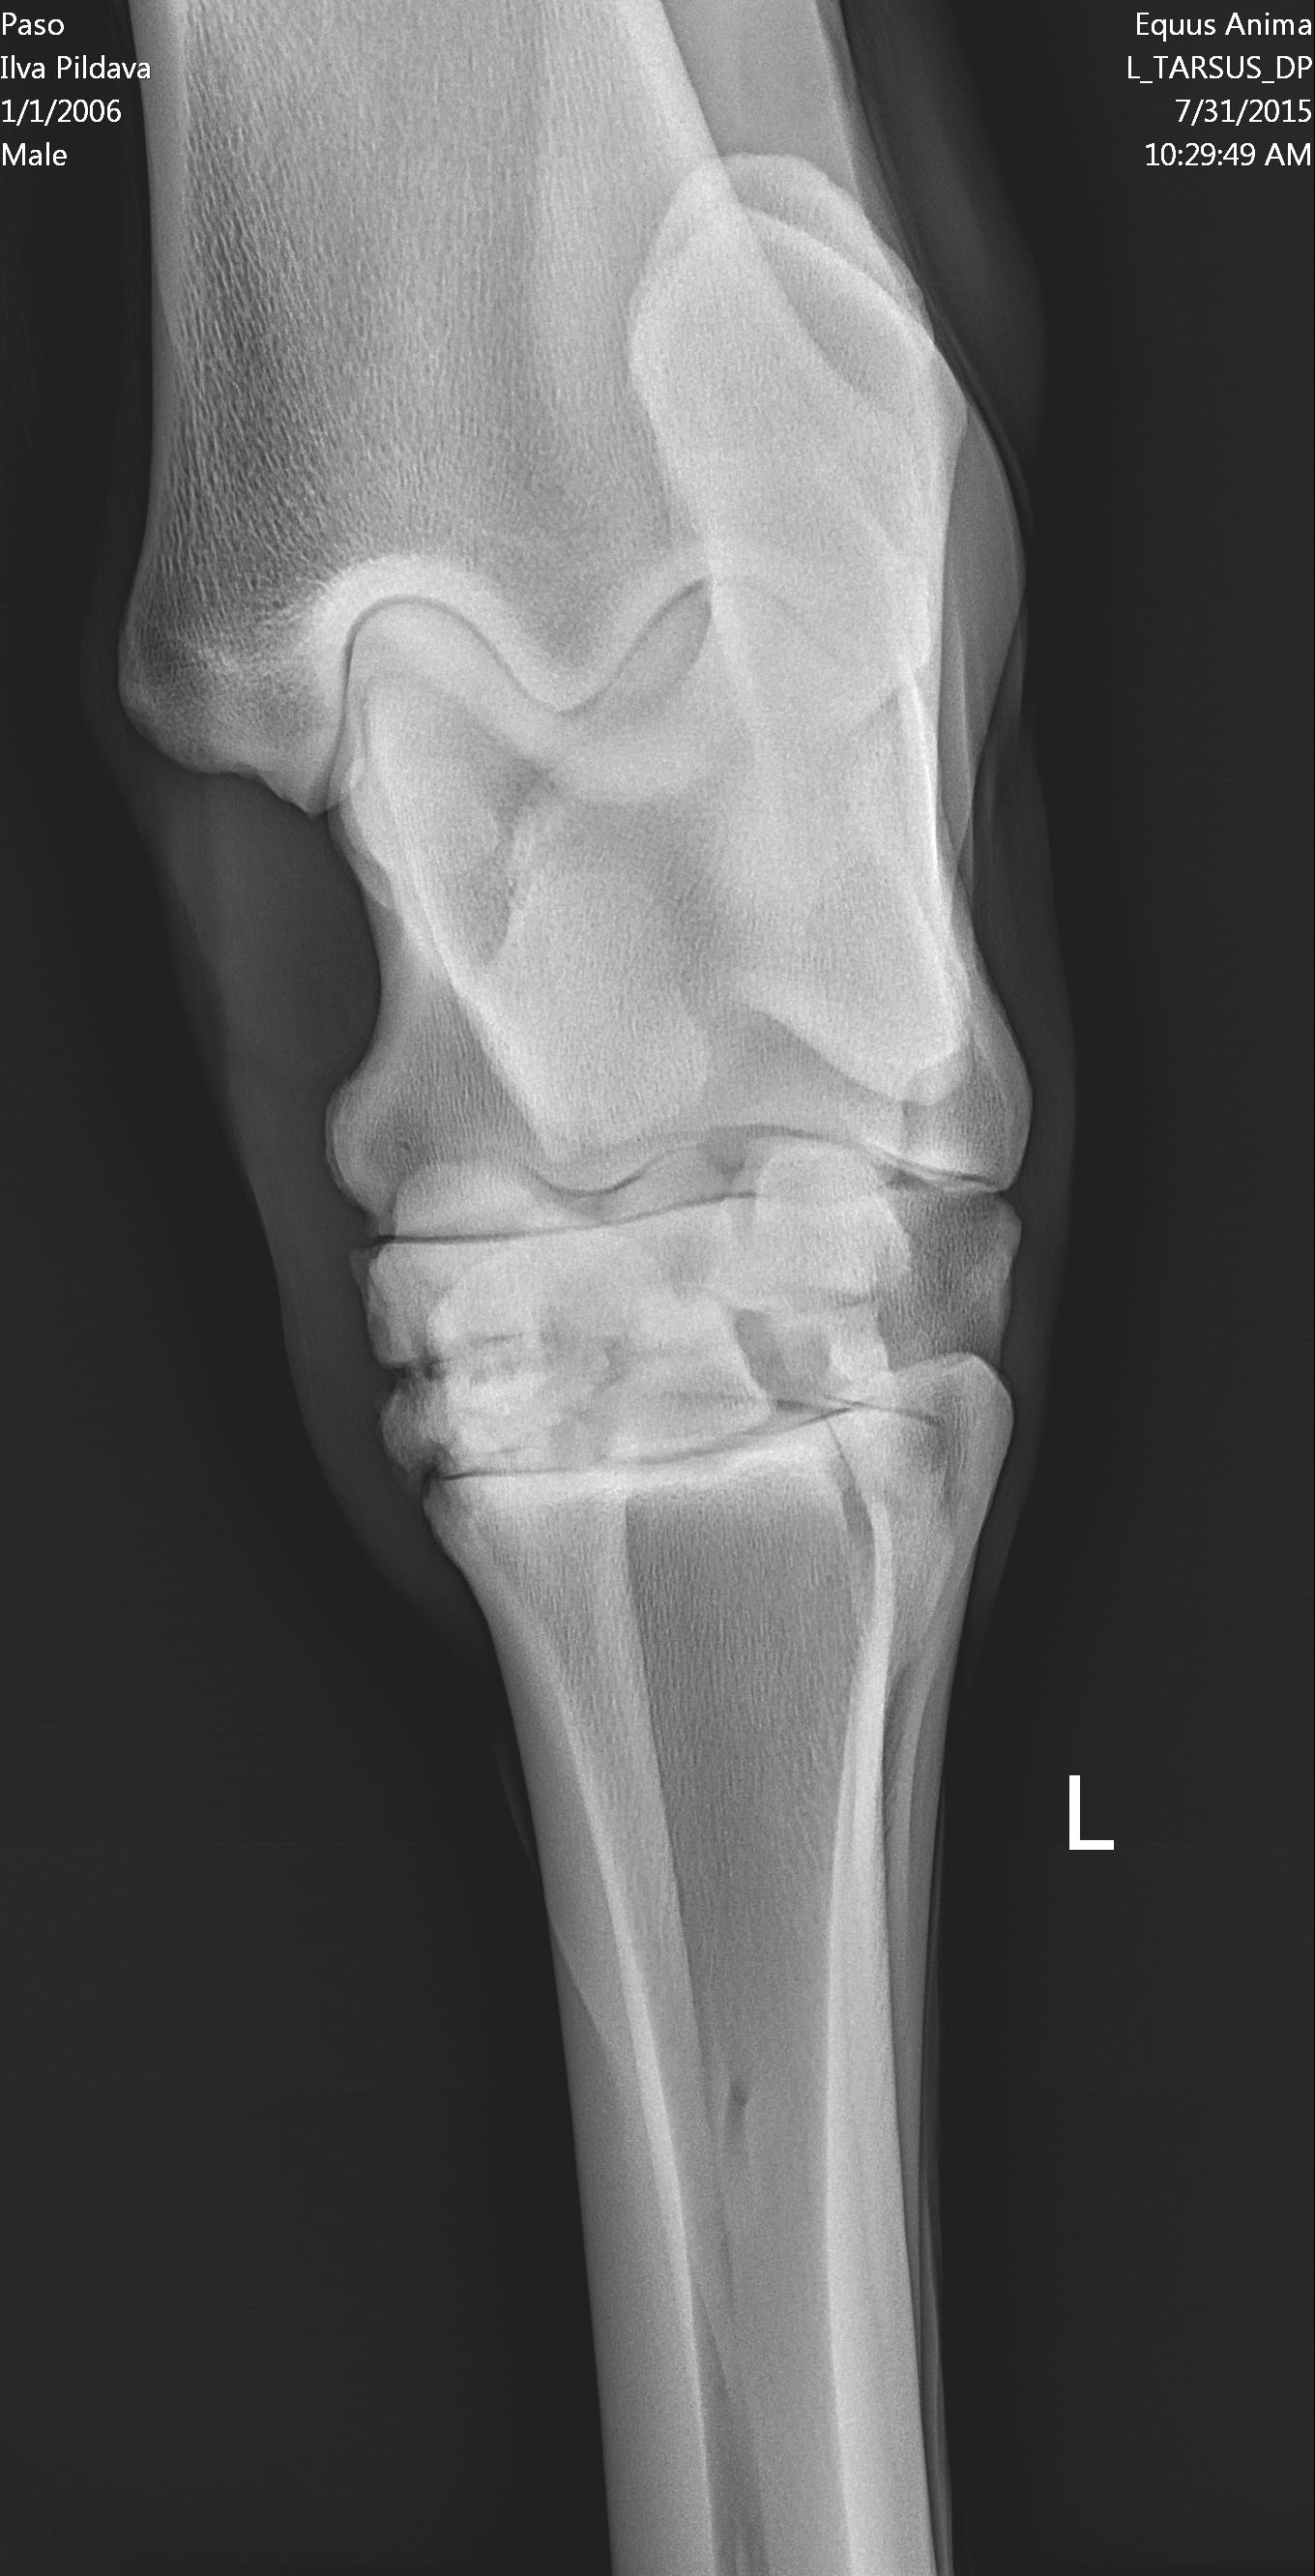

U majei loshadi ( 10 let) kastrat, v proslom godu obnaruzili spat I sdelali kurss Tildren, 16.10.2017. ehso odin kurss, daju polgoda eto http://ru.eggersmann.info/432_/132_Profi_Gelenk_aktiv.html, I vot kakije u loshadi rentgeni po datam. Prigaju do 110 cm, edu na sorevnavanije, idjot on horosho. esli stojal v bokse , snachala hromaet,no potom 2-4 minuti v risi i prohodit. Ja bi hotela prigatj vishe,no bojus ,mozno li. Letom dva raza bila ,chto v trenirovke zahramal ochen silno,no cerez paru chasov ,vsjo proslo.

Vopros,kakije prognozi, chto esje davatj I kakje nagruzki mozno? U nas malo opita s Tildren,potomu kazdij govorit svojo.